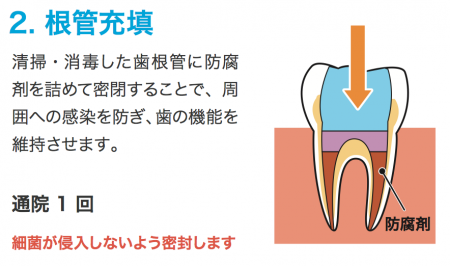

根管治療が進むと根管に密閉し感染の再発を

防ぐために特殊な充填材を詰めます